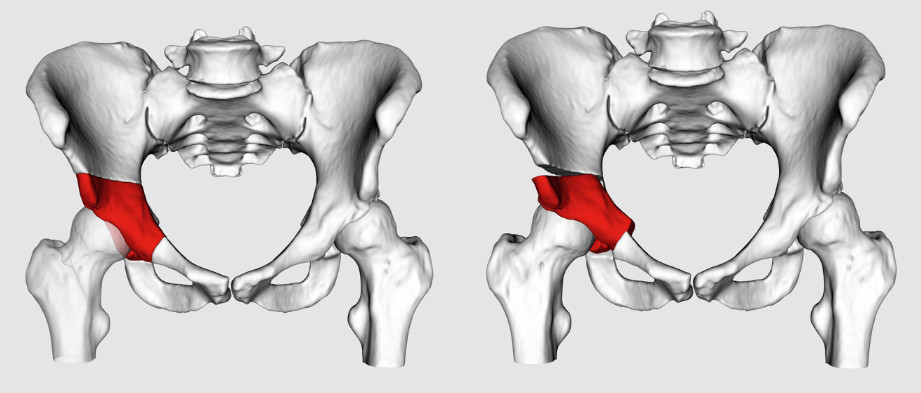

Največje zasluge za razvoj moderne rekonstrukcijske kirurgije na kolku ima skupina ortopedov z Univerzitetne bolnišnice v Bernu v Švici pod vodstvom profesorja Reiholda Ganza, ki je najprej v sredini 80. let prejšnjega stoletja predstavila periacetabularno osteotomijo. To je rekonstrukcijski poseg, s katerim izboljšamo pokritost kolčnega sklepa z displastičnim acetabulom. Periacetabularna osteotomija je zaradi zapletene trodimenzionalne oblike medenice in neposredne bližine več pomembnih žilno-živčnih snopov za spodnji ud tehnično zahteven kirurški poseg. Potem, ko prekinemo medenično kost na več mestih okrog displastičnega acetabula, sproščeni kostni del skupaj z acetabulom postavimo v biomehansko boljši položaj (slika 3).Z različnimi tipi osteotomij na medenici in na stegnenici lahko zdravimo tudi druge bolj redke razvojne nepravilnosti in deformacije kolčnega sklepa.

Slika 3. Periacetabularna osteotomija

a – fragment z acetabulom (označen rdeče na grafiki) sprostimo s pomočjo dlet in žage

b – acetabulum postavimo v biomehansko boljši položaj